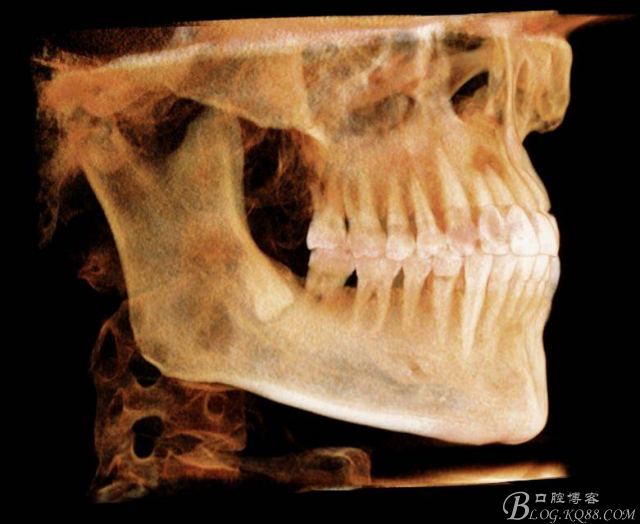

錐形束CT在智齒拔除中的應用

48未萌出,47遠中可探及深約7mm的牙周袋。頰側47、48之間牙齦紅腫,有少量血性滲出。X線根尖片顯示:48牙冠反轉倒置,47遠中牙槽骨吸收明顯。CBCT顯示:48牙冠近中面位于下頜管內。

圖5. 48的三維視圖